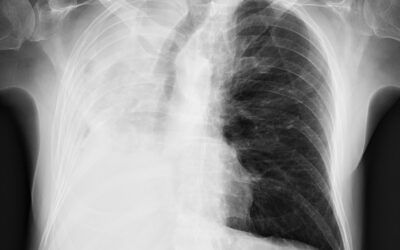

პაციენტი 57 წლის მამაკაცი, მოგვმართა ონკოლოგის რეკომენდაციით დიაგნოსტიკური ფიბრობრონქოსკოპიის ჩასატარებლად ბიოფსიით, რაც ჩატარდა 23.02.2026 წ. 2 კვირის შემდეგ განვითარდა ჰაერის მწვავე უკმარისობა მოხრჩობის შეგრძნება, სტრიდორული სუნთქვა. ჩატარებული გულმკერდის...